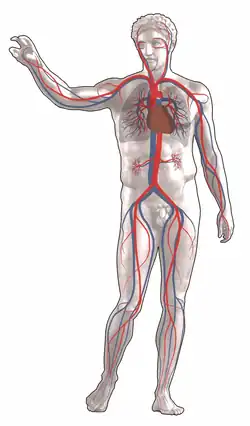

Blood circulation: Red = oxygenated, blue = deoxygenated

Blood circulation: Red = oxygenated, blue = deoxygenated -

Circulatory system

Blood is circulated around the body through blood vessels by the pumping action of the heart. In humans, blood is pumped from the strong left ventricle of the heart through arteries to peripheral tissues and returns to the right atrium of the heart through veins. It then enters the right ventricle and is pumped through the pulmonary artery to the lungs and returns to the left atrium through the pulmonary veins. Blood then enters the left ventricle to be circulated again. Arterial blood carries oxygen from inhaled air to all of the cells of the body, and venous blood carries carbon dioxide, a waste product of metabolism by cells, to the lungs to be exhaled. However, one exception includes pulmonary arteries, which contain the most deoxygenated blood in the body, while the pulmonary veins contain oxygenated blood.

Additional return flow may be generated by the movement of skeletal muscles, which can compress veins and push blood through the valves in veins toward the right atrium.

The blood circulation was described by William Harvey in 1628.[20]